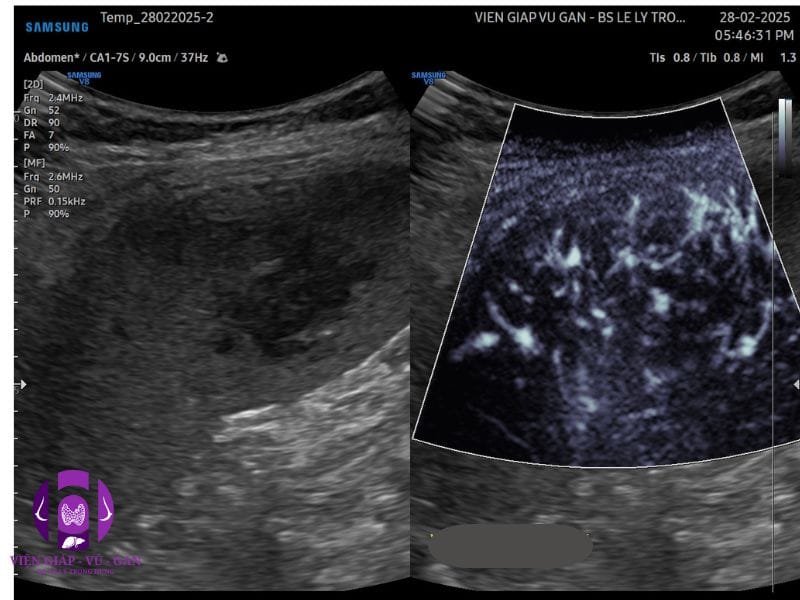

SIÊU ÂM BỤNG:

Lách: không to, cực dưới có khối echo dày, không đồng nhất, bờ đều, giới hạn rõ, kt# 40x30x25mm, doppler ghi nhận mạch máu phân bố rải rác ngoại vi và trung tâm.

SIÊU ÂM:

• Khối echo dày, đồng nhất, giới hạn rõ, không tăng âm phía sau.

• Doppler: tín hiệu mạch máu ít. (80% không có tín hiệu mạch)